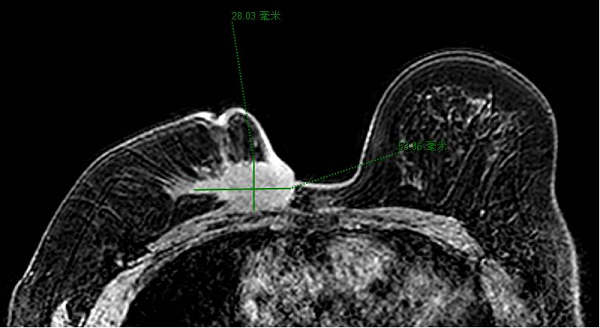

今年四月,命运给陈女士开了一个残酷的玩笑,她被确诊为右乳腺癌伴腋窝淋巴结转移。此时的她,乳房局部已出现破溃。经过6期的针对性化疗后,肿物虽稍有缩小,但鸡蛋大的肿瘤与胸骨紧邻的复杂病情,仍让治疗陷入两难。

肿瘤紧紧紧贴着胸骨,就像顽固的“钉子户”,传统治疗方法难以在这场“拆迁”中,兼顾去除病灶以及体表完整。因此,制定一个能平衡二者关系的周密治疗方案,成为决策的关键。